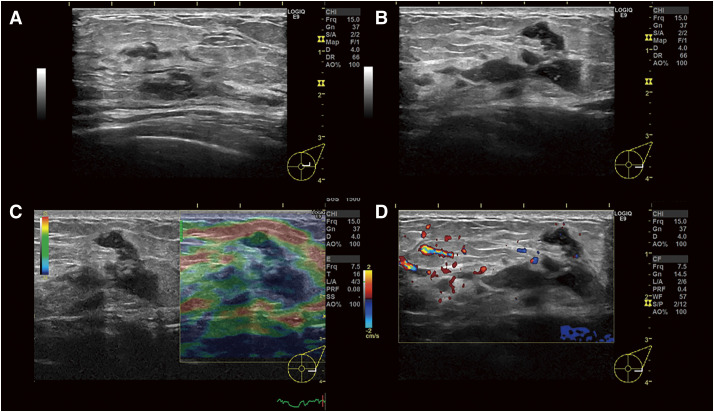

Case presentation: We report the case of a 36-year-old Japanese woman with granulomatous mastitis due to Mycobacteroides abscessus who had not undergone surgery and was not immunosuppressed. She presented with a chief complaint of pain and swelling in her left breast for 1 month. Mammography showed asymmetrical focal increased density, and ultrasonography showed an irregular hypoechoic area in the left 3 o'clock position. Contrast-enhanced magnetic resonance imaging showed segmental non-mass-enhancement. Ultrasound-guided vacuum-assisted biopsy with pathology revealed granulomatous mastitis. Ziehl-Neelsen staining revealed red-staining bacilli. The patient was followed up for observation because her breast pain had decreased after the examination, and there was no redness or fever. However, the breast pain has not completely disappeared, and intermittent purulent discharge from the biopsy site persisted for 5 months. Hence, two 12-Fr drains were inserted along the ductal dilatation-like hypoechoic area. Imipenem, amikacin, and clarithromycin were administered for 8 days. After 8 days of this therapy, the patient developed a drug-associated rash; therefore, antimicrobial therapy was discontinued, and the drains were removed. Her symptoms improved, and magnetic resonance imaging after 1 month showed that the previous imaging findings in her left breast had disappeared. At the time of writing, 18 months have passed since treatment, and no recurrence has been observed.